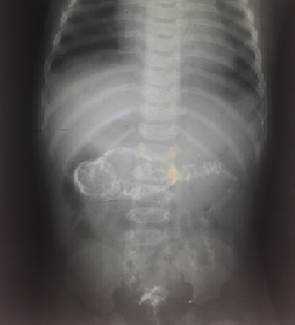

На рисунках 4 и 5 представлена картина кишечной инвагинации при рентгенологическом исследовании.

Рис. 5. Ирригограмма после опорожнения толстой кишки - симптом «кокарды»

Комментарий: для дополнительной диагностики инвагинации кишечника допустимо использование рентгенографии (рентгеноскопии). При инвагинации кишечника на обзорных рентгенограммах органов брюшной полости, выполненных в вертикальном положении может отмечаться малое газонаполнение правого нижнего квадранта живота и признаки кишечной непроходимоти - расширенные петли кишечника с уровнями жидкости. В случае перфорации стенки ущемленной кишки и развитии перитонита - определяется свободный газ в брюшной полости (серповидная полоска просветления над печенью). Однако подобная рентгенологическая картина неспецифична для инвагинации кишечника. Более полные сведения при подозрение на инвагинацию кишечника дает контрастная ирригография. В качестве контраста в случае подозрения на инвагинацию кишечника целесообразно использование воздуха (пневмоирригография). При выполнении пневмоирригографии ребенка укладывают на стол рентгенологического аппарата в горизонтальном положении. Нагнетание воздуха в ампулу прямой кишки производят баллоном Ричардсона через катетер. Воздух в кишку нагнетают медленно и осторожно. По мере заполнения воздухом толстой кишки головка инвагината определяется в виде гомогенной тени с четкими контурами. Расположение тени зависит от анатомического типа внедрения. Равномерное заполнение толстой кишки воздухом и проникновение его в начальный отдел подвздошной кишки позволяет исключить наличие инвагината в этом отделе кишечника, но не снимает диагноза тонкокишечного внедрения.